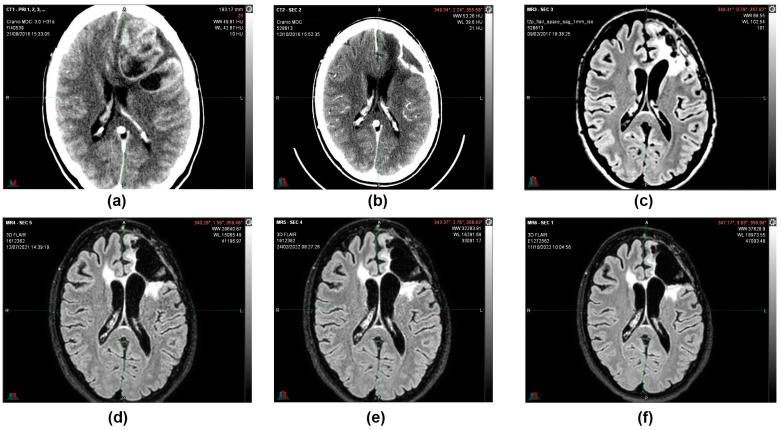

In August 2016, in the emergency department, a 36-year-old woman, after 15 days of headache and unresponsiveness to non-steroidal anti-inflammatory drugs (NSAID), underwent a computed tomography scan (CT scan). The CT scan of the brain, performed with contrast medium, showed, in the left fronto-parietal area, two voluminous formations and inhomogeneous contiguous focalities of 52 × 41 mm and 40 × 20 mm, respectively, characterized by irregular peripheral impregnation and contextual necrotic–colliquative areas, with surrounding perilesional digitiform hypodensity, compression of the lateral ventricle, and contralateral shift of the midline structures (1 cm) (Figure 1).

Encephalon/Cranium CT scan with contrast medium performed postoperatively on 12 October 2016 showed an apparently reduced liqueur-like collection with associated wall impregnation. Posterior to the surgical cavity, there is an approximately 2 cm hyperdense solid nodule characterized by contrast-enhancing impregnation (Figure 2).

During the follow-up, quarterly visits, clinical-instrumental checks, and monthly blood and biochemistry tests were carried out. At the end of the first cycle of O2O3 therapy (9 February 2017), the 2 cm residual tumor mass that was present 3 months before was no longer visible on the brain magnetic resonance imaging (MRI) (Figure 3), and the stable-negative tumor mass was confirmed with the MRI on 11 October 2022 (Figure 4).

MRIs were done in subsequent periods (12 July 2021 and 11 October 2022), confirming that the morphological picture remained stable and that the patient was considered cured (Figure 5).